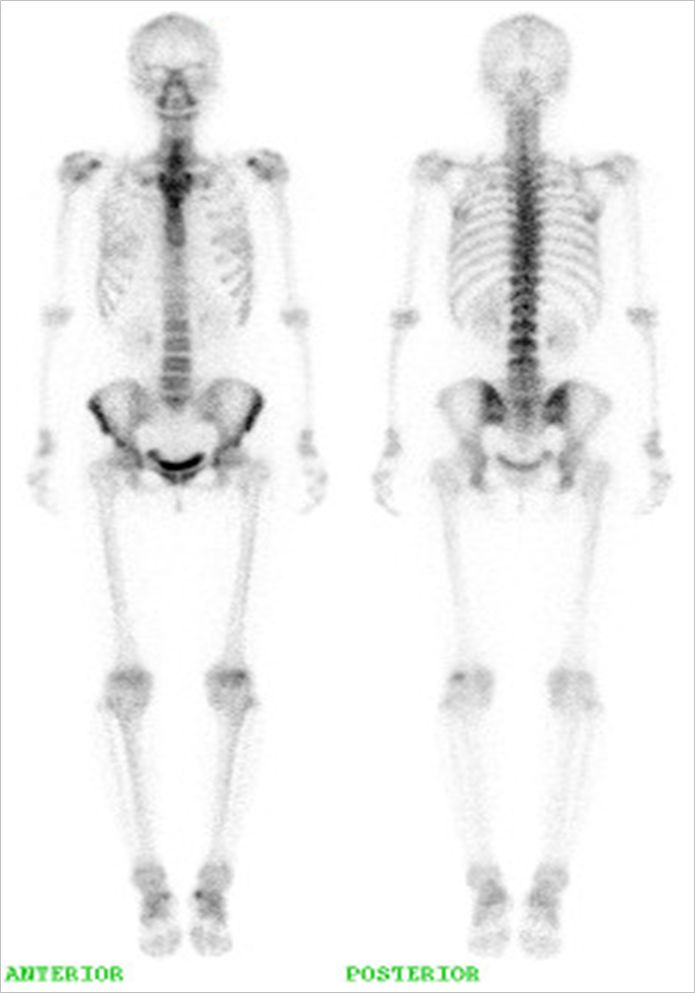

<全身の骨の検査>

骨の検査では、全身の骨の代謝を調べることによって、骨腫瘍や骨の炎症の状態、他の臓器からの骨転移病変などの診断を行います。